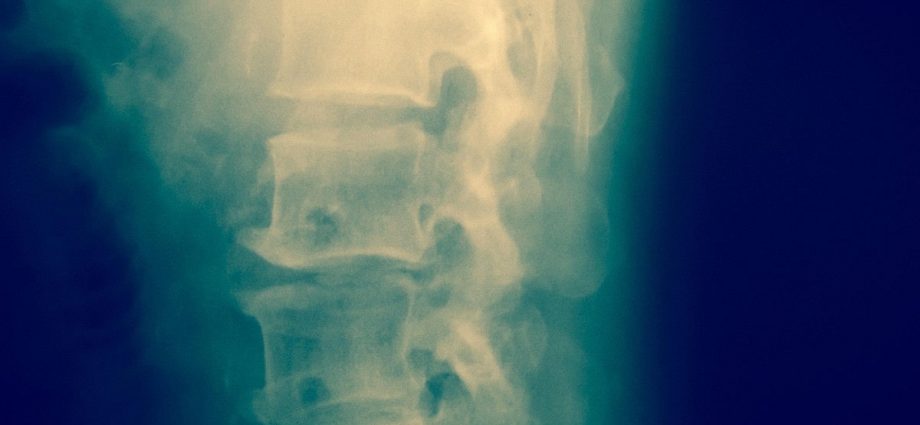

Tests in 17 people without a spinal cord injury showed that the decoder could cue movement in their lower legs using spinal cord stimulation, researchers reported in the Journal of NeuroEngineering and Rehabilitation.

Using those brain waves, people were able to move their lower leg by just thinking about it, with an external electrode stimulating their spinal cord into producing the movement, researchers reported.

The study is a first step toward developing a brain-spine interface that uses real-time brain waves and spinal cord stimulation to promote movement in people with a spinal cord injury, researchers said.